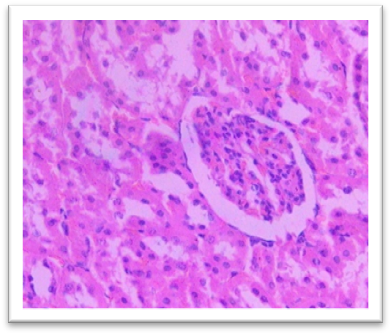

Histomorphometry

At the end of the study, femur bones were dissected and fixed for histological analysis. Group I (Normal) showed normal bone architecture, with well-organized chondrocytes. Group II (Lanthanum Carbonate only) maintained normal bone growth. Group III (Chronic Kidney Disease control) exhibited fibrocartilaginous changes, disorganized collagen, and impaired endochondral ossification, characteristic of Chronic Kidney Dosease. Groups IV (150 mg/kg), V (250 mg/kg), VI (500 mg/kg), and VII (750 mg/kg) demonstrated varying degrees of improvement in bone structure, with the highest dose (Group VII) showing the most significant restoration of normal bone architecture. Histomorphometry of bone: In Group III, designated as positive control for Chronic Kidney Disease, histomorphometric analysis of femur revealed significant fibrocartilaginous changes within the articular cartilage, characterized by an increased fibroblast, loss of chondrocyte organization, and disorganized collagen deposition. Furthermore, the growth plate exhibited a marked increase in the thickness of the hypertrophic zone, suggesting impaired endochondral ossification. Similar findings were observed by Saito et al. (2021) who observed that in Adenine-induced Chronic Kidney Disease, there was a reduction in bone minera density (BMD) throughout the body as well as in the femur Furthermore, micro- computed tomography (micro-CT) analysis revealed a decline in the microstructural integrity of the cortical bone, which contributed to diminished bone strength in both cortical and trabecular regions. Ferrari et al. (2014) reported that the bone microarchitecture in rats subjected to Adenine-induced renal failure exhibited significant alterations, characterized by a reduced trabecular number and an increased trabecular separation. Additionally, the presence of fibrosis was noted in the rats with Adenine-induced renal failure. Ni et al. (2018) performed a histomorphometry analysis and revealing that the bone mineral density (BMD) in the femurs of rats with Chronic Kidney Disease (CKD) was markedly lower than that observed in the control (CTL) group. Additionally, significant bone loss was evident in both cortical and trabecular bone parameters of the femurs.  Lanthanum Carbonate @150mg/kg, 250mg/kg, 500mg/kg and 750 mg/kg, histomorphometric analysis revealed very minimal to nearly absent fibroblast proliferation in the articular cartilage, characterized by the absence of fibroblast- like cells and well-maintained chondrocyte organization. Additionally, the growth plate exhibited moderate proliferation of the hypertrophic zone, indicating significant improvement in endochondral ossification compared to the positive control group (Group III) and lower-dose treatment groups. These findings suggest that the highest dose of Lanthanum Carbonate (750 mg/kg) may provide the most effective therapeutic benefits in mitigating bone-related pathological changes associated with Chronic Kidney Disease Yajima et al. (2018) demonstrated that Lanthanum Carbonate enhanced the mineralization of the periosteal surface, augmented bone mass within the intracortical resorption areas, and improved mineralization on the minimodeling surface at the endocortical region. They concluded that Lanthanum Carbonate has the potential to bolster cortical stability in patients with Chronic Kidney Disease (CKD)..

Fig. 27 Group IV Femur showing moderate fibroblastic changes at articular cartilage and moderate proliferation of hypertrophic zone under H & E 400X.

Fig. 28 Group V, Femur exhibited mild fibroblastic changes at articular cartilage and moderate proliferation of hypertrophic zone under H & E 400X.

Fig. 29 Group VI showing minimal fibroblastic changes at articular cartilage and moderate proliferation of hypertrophic zone under H & E 400X.

Fig. 30 Group VII Femur, showed very minimal or nearly absent lesions such as fibroblastic changes at articular cartilage and moderate proliferation of hypertrophic zone under H & E 400X.